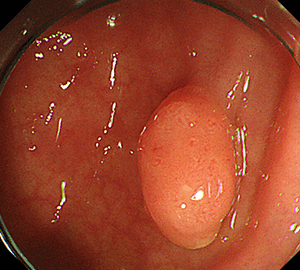

1:ポリープを見つけ、NBI併用拡大観察をした後…1:ポリープを見つけ、NBI併用拡大観察をした後…

2:ポリープ直下の粘膜下層に局注液を注入します。2:ポリープ直下の粘膜下層に局注液を注入します。

3:ポリープをスネアに通し、周囲の正常粘膜を入れて病変を絞扼し…3:ポリープをスネアに通し、周囲の正常粘膜を入れて病変を絞扼し…

4:通電して切除し、周囲を観察して病変の遺残がないことを確認します。4:通電して切除し、周囲を観察して病変の遺残がないことを確認します。

5:切除面をクリップで縫合閉鎖し、回収した検体の病理検査を行います。5:切除面をクリップで縫合閉鎖し、回収した検体の病理検査を行います。